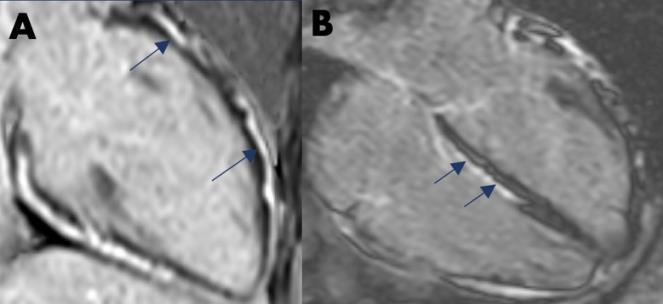

CASE PRESENTATION: A 32-year-old man presented to the emergency room following 12 hours of progressively worsening acute sharp right-sided chest pain that worsened with supine positioning and improved with seated or standing positioning. He was notably hypertensive (142/84 mmHg), tachycardic (108 beats/min), afebrile (99.4 F), and tachypneic (35 breaths/min). His electrocardiogram showed diffuse ST segment elevations in anterior, anterolateral, and inferior leads and diffuse PR segment depressions (Figure 1). The physical exam was remarkable for diaphoresis, tachypnea, temporal muscle wasting, symmetrically enlarged thyroid without palpable nodules, and tenderness in the subxiphoid area.

Initial labs showed an elevated WBC count of 17.8K [Normal Level (NL) 4.5–11.0 K/µL], troponin-I of 0.047 ng/mL (NL <0.031 ng/mL), and ALP of 140 U/L (NL 38–126 U/L). The patient had normal renal function and electrolytes. Repeat troponin-I was 37.5 ng/mL. CRP and ESR were 26.79 mg/L (NL < 5.1 mg/L) and 0 mm/hr, respectively. A chest X-ray showed a normal cardiac silhouette and bilateral lower lung volumes with increased vascular markings. Chest computed tomography (CT) with contrast showed presence of a prominent soft tissue mass within the anterior mediastinum suggestive of persistent thymus, and no evidence of acute aortic pathology or central pulmonary embolism. The patient’s cardiac magnetic resonance imaging (CMR) showed large amounts of transmural myocardial edema at the basal anterior, basal anteroseptal, mid inferior, mid inferoseptal, mid inferolateral, apical inferior, and apical inferoseptal segments (7/17 segments of the 17 segment ACC/AHA model). There was no evidence of concomitant late gadolinium enhancement (LGE) in these segments. There was a large amount of diffuse circumferential LGE of the pericardium, with a maximal pericardial wall thickness of 3.7 mm. Concomitant with LGE, there was a large amount of patchily-distributed pericardial edema

Up to 20% of patients with hyperthyroidism have cardiac symptoms. Although pericardial disease as a complication of thyrotoxicosis is rare, all patients presenting with signs of myocarditis/pericarditis should undergo screening for the extracardiac symptoms of hyperthyroidism that were present in our patient. Although most reported cases in the literature were confirmed by endomyocardial biopsy (EMB), CMR can offer the diagnostic yield without procedural risks. The presence or absence of myocardial LGE on CMR is important for risk stratification of myopericarditis, as patients showing LGE have a higher risk of major adverse cardiovascular events (MACE) (Hazard Ratio = 2.2), with the best outcomes predicted in patients with EF > 40% and no LGE. Although our patient showed no myocardial LGE and preserved EF, he had significant transmural myocardial edema. These findings are consistent with a very acute and early presentation, with a need for repeat CMR in the follow-up period to reassess for LGE. Ventricular arrhythmia risk secondary to lymphocytic infiltration in myocarditis is well reported but usually more commonly associated with Giant Cell Myocarditis (GCM) and cardiac sarcoidosis. Arrhythmias are less common in isolated pericarditis or minimal myocardial inflammation and are usually supraventricular (SV) in origin (<10%), with atrial fibrillation being the predominant SVT However, despite the low incidence of sudden cardiac death (SCD), SVT, or VT, especially in the acute inflammatory phase, beta blockers have been recommended for risk reduction and treatment of hyperthyroidism symptoms. Our patient was started on metoprolol tartrate for both possible risks of arrhythmia and symptom treatment of hyper thyrotoxicosis.

Figure 1: Electrocardiogram showing diffuse ST segment elevations and PR segment depressions